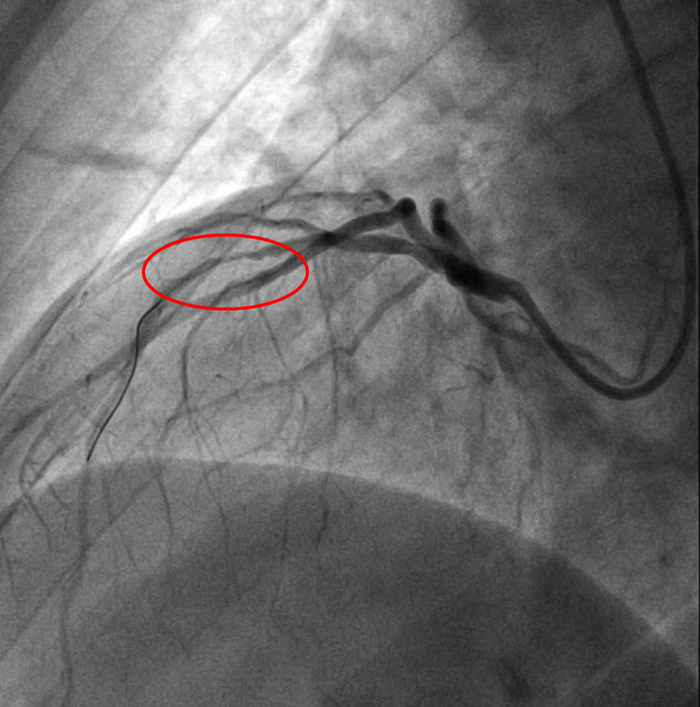

Итак на коронарографии такая картина при первой же съемке:

Стенозирование передней межжелудочковой артерии (ПМЖА) в начальном (проксимальном сегменте), инфаркты при полном закрытии ПМЖА в этом сегменте часто фатальные, либо приводят к инвалидизации

С учетом данных ВСУЗИ проводится сразу прямое (без предварительной предилатации баллоном) стентирование ПМЖА с покрытием ствола левой коронарной артерии.

Получаем такой результат